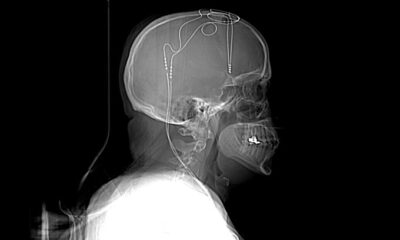

The team set out to understand how this happens by studying microscopic worms known as C. elegans. They created a system to manipulate the amount of MANF in C. elegans.

The team discovered that MANF plays a key role in the cell’s disposal process by helping to break down the accumulated proteins, keeping cells healthier and clutter-free. Increasing MANF levels also activates a natural clean-up system within cells, helping them function better for longer.